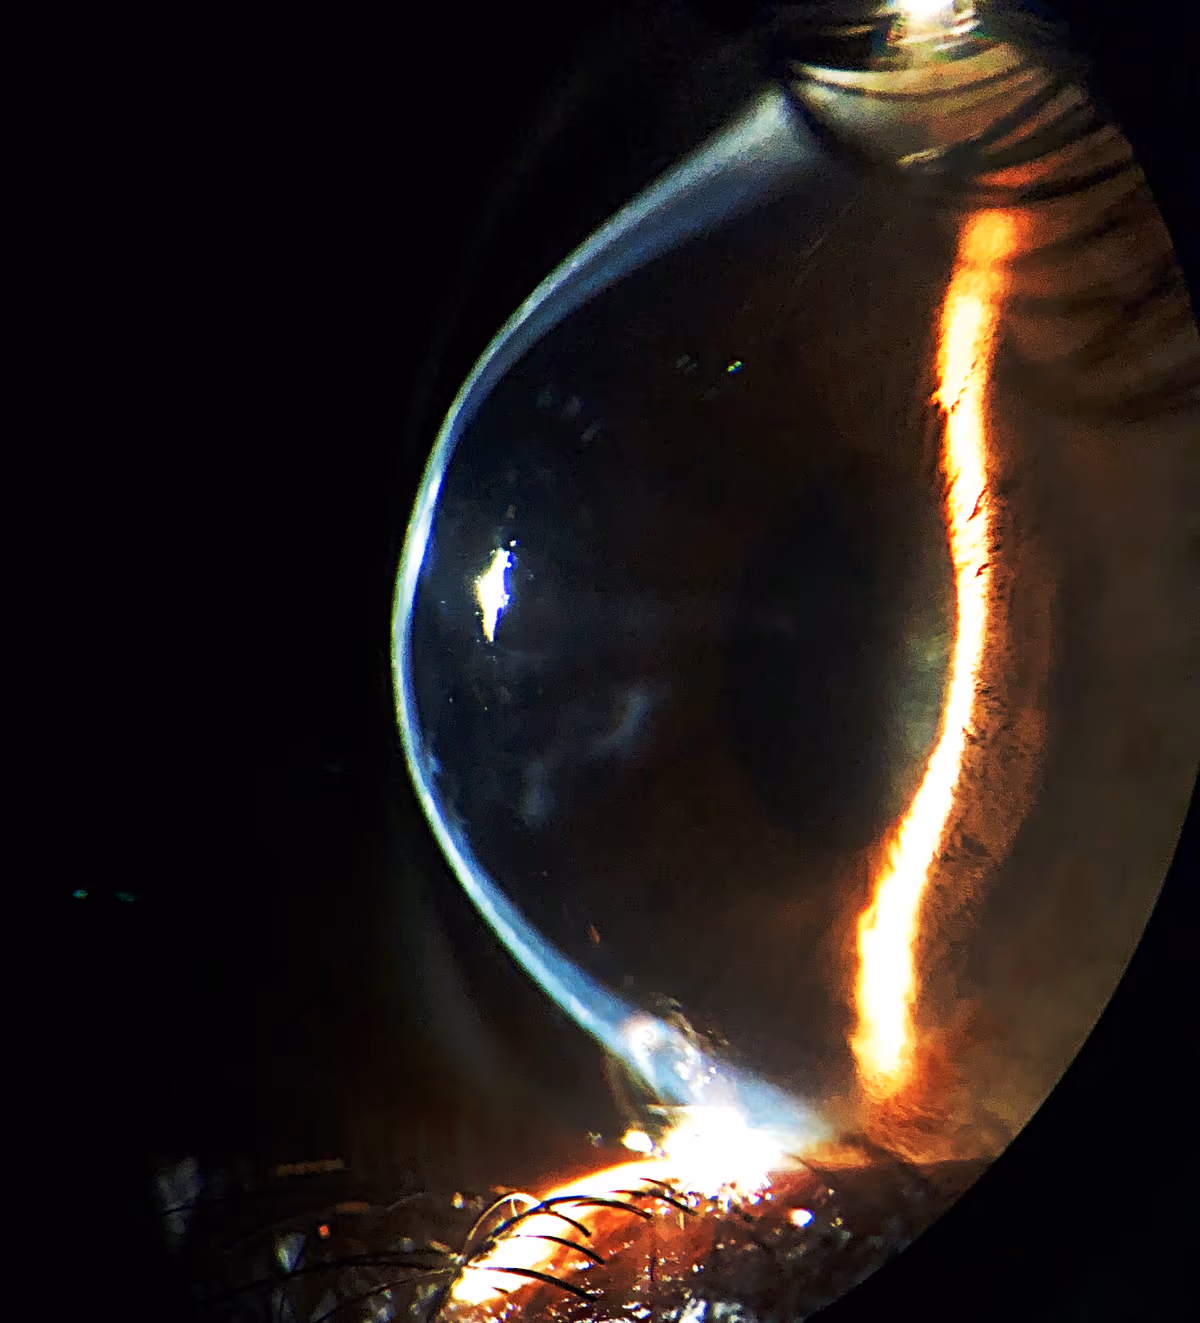

Dois modelos são utilizados mundialmente: o Keraring (Mediphacos, Brasil) e o Anel de Ferrara. Ambos são segmentos semicirculares de acrílico inerte (PMMA) com geometrias ligeiramente diferentes, indicados conforme o formato e a localização do cone avaliados pela tomografia de córnea.

O objetivo principal é regularizar a topografia corneana, aplanando o centro do cone e redistribuindo a curvatura. Isso reduz o astigmatismo irregular, melhora a visão sem correção na maioria dos casos e facilita a adaptação posterior de óculos ou lentes de contato.